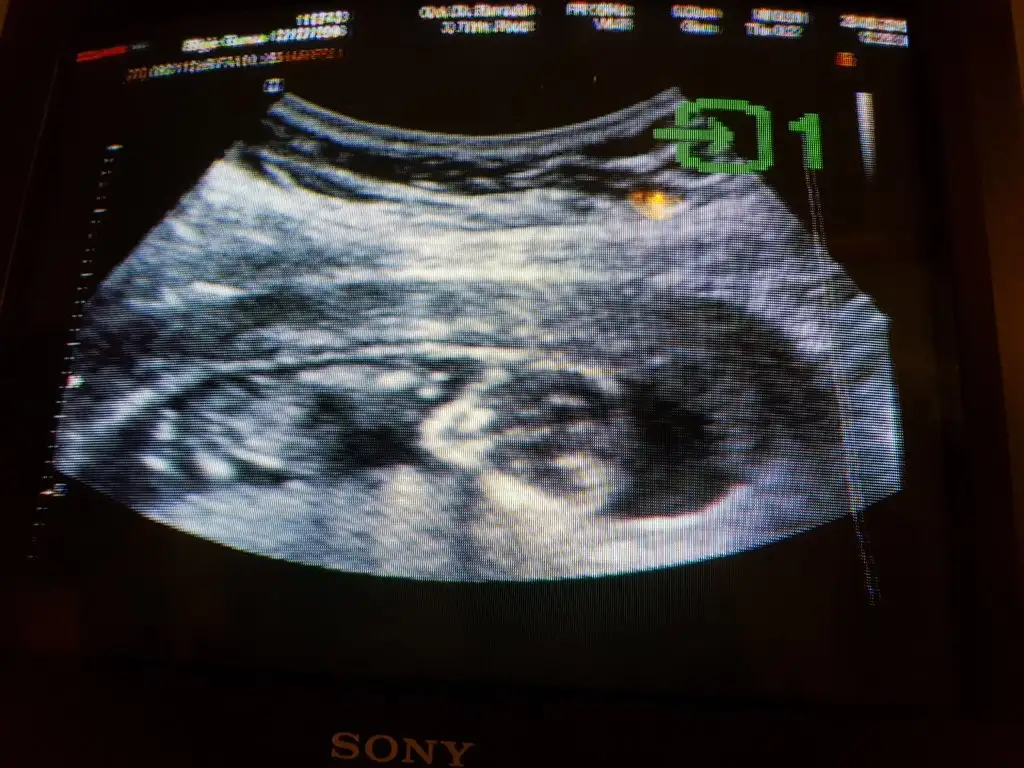

Nub yöntemine göre cinsiyet tahmini

Ama şüpheli tahminim kızlar genelde aşağı doğru ama bu fındığınki karşıya doğru erkekte olabilir 🙂

• Picture_20195619105605.webp

Picture_20195619105605.webp

20,3 KB · Görüntüleme: 100